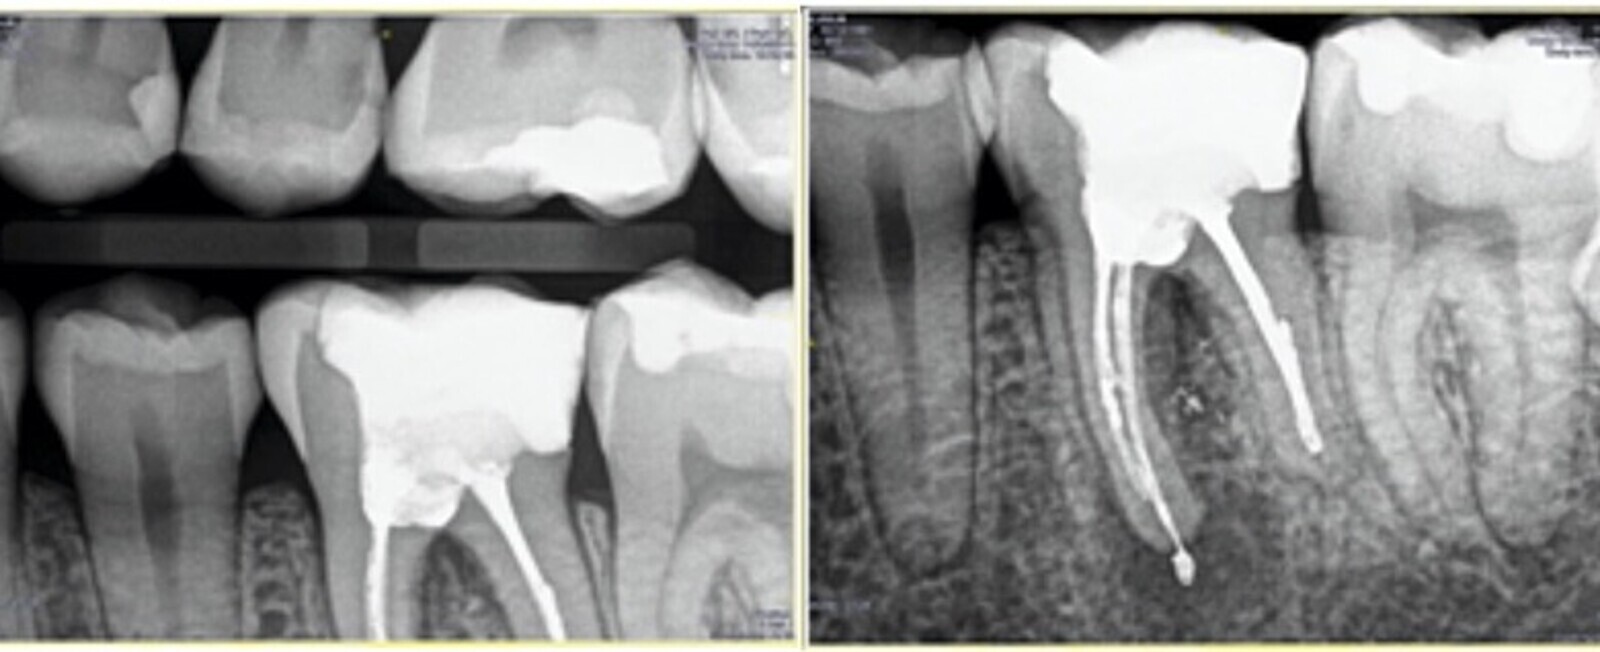

Fig. 5. Sellado de la perforación con Biodentine.

Durante la apertura cameral se localizó una perforación en furca que se selló con un material biocerámico.

Fig. 7. Radiografía final del retratamiento no quirúrgico del 3.6. con su restauración indirecta cementada.